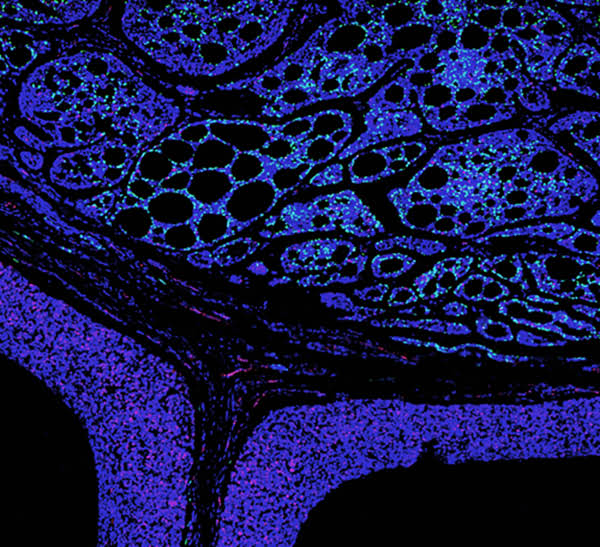

為促進科學(xué)文化發(fā)展,活躍專委會的科技人文氛圍,培養(yǎng)科研工作者的創(chuàng)新意識,激發(fā)他們發(fā)現(xiàn)美、創(chuàng)造美的熱情和興趣,本次年會特別增加了一項“生命的藝術(shù)——首屆年度顯微圖片展”活動。在專委會發(fā)出征稿通知之后,來自全國近20 所院校的師生積極響應(yīng),共投稿顯微攝影作品125 幅。經(jīng)以王松靈院士為主席的九位審讀專家組成員在線上線下的認真審閱和討論,從圖片的原創(chuàng)性、科學(xué)性和藝術(shù)性三個方面進行綜合考量,最終確定年度圖片1 幅,年度提名圖片20 幅。在此匯集成冊,與各位同仁分享、交流。

這些作品幾乎均為創(chuàng)作者在日??蒲泄ぷ髦幸圆煌募夹g(shù)手段捕捉到的微觀生命瞬間,科學(xué)的“透鏡”似乎為我們展現(xiàn)出一幅幅藝術(shù)的“魔幻”,一邊是細胞、分子層面的微觀抵達,另一邊好似一塊既陌生又熟悉的“優(yōu)詩美地”。這里,本是科學(xué)嚴謹?shù)念I(lǐng)地,因為其關(guān)乎生靈,便開啟人們自由逸放的審美思緒。在此,我們驚嘆中國古代哲學(xué)體系中“天人合一、道法自然”的天道規(guī)律。原來早于現(xiàn)代科學(xué),這種“盡精微而致廣大”的宇宙觀便已根植于我們生存的大地。感謝各位作者以他們現(xiàn)代技術(shù)的視野,為我們定格生命律動的瞬間,張揚蓬勃的藝術(shù)活力。換一個視角,生命的風景便呈現(xiàn)“天地人”的和諧和統(tǒng)一,換一種思路,生命的哲學(xué)便更能詮釋苦難與幸福的非凡境遇。